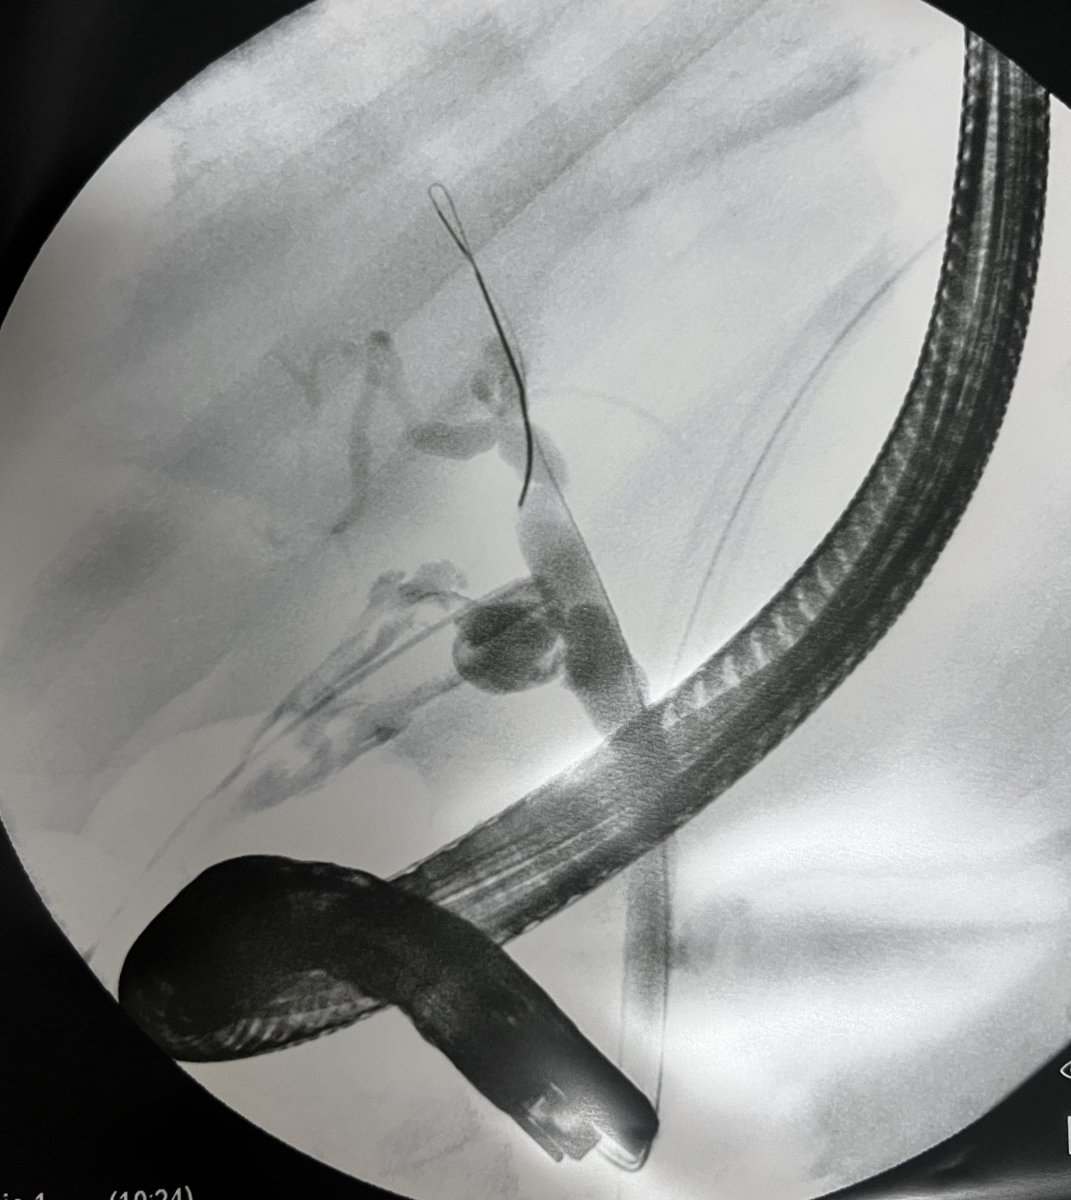

⚡️Tips to improve lift for resection⚡️

1. SSLs: No injection if margins are visible or < 20 mm

2. 10-30 mm lesions: central injection

3. Dominant lesions: start from accessible region

4. >30: inject, cut, repeat

Agents:Fig